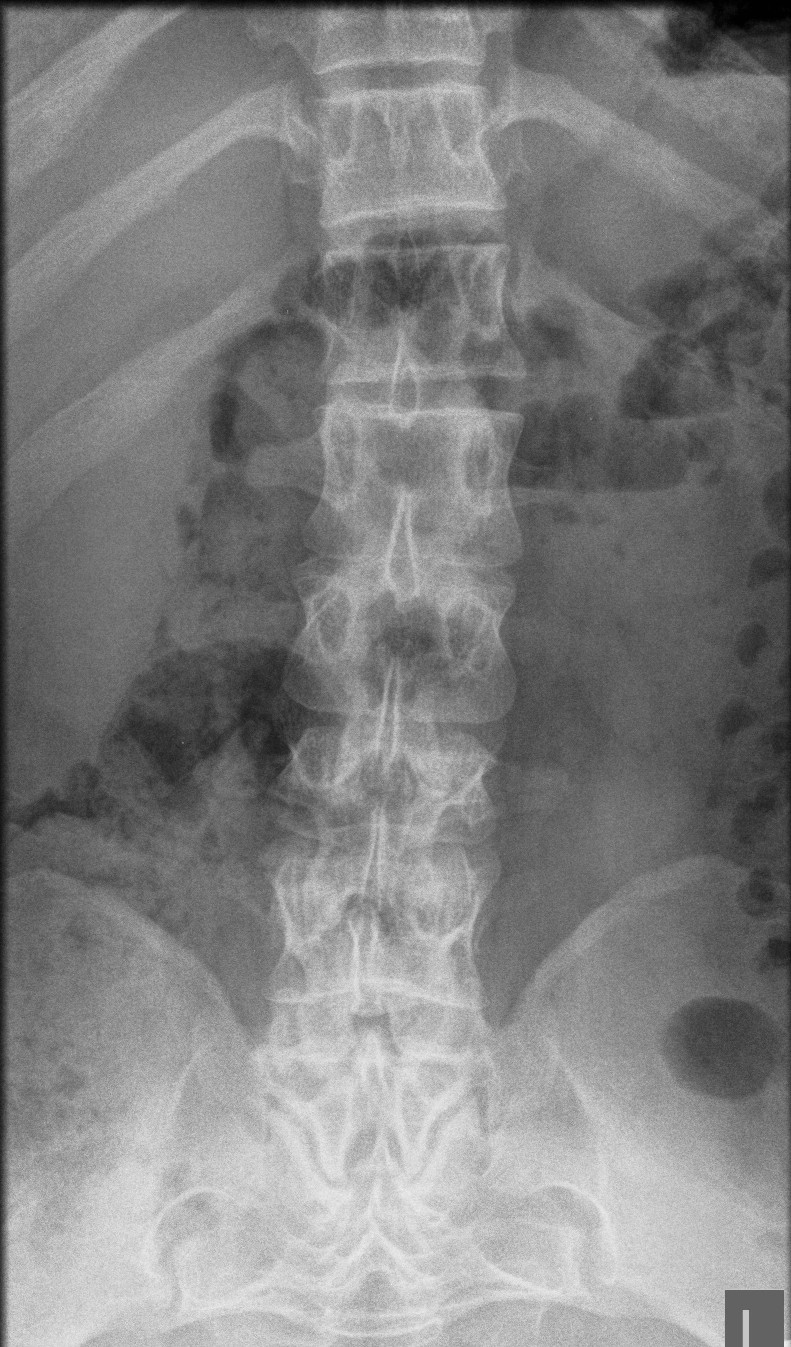

Pelvis

Square iliac bones

- " elephant ears"

- narrow siatic notch

Champagne-glass pelvic cavity

- the pelvis is wider than it is deep

Spine

Spinal canal stenosis

- decreased inter-pedicular distance

- narrows from L1 down (normally increases)

- short pedicles

Platyspondyly

- bullet shape vertebrae

- anterior inferior body beak T12- L2

- posterior scalloping of vertebral bodies